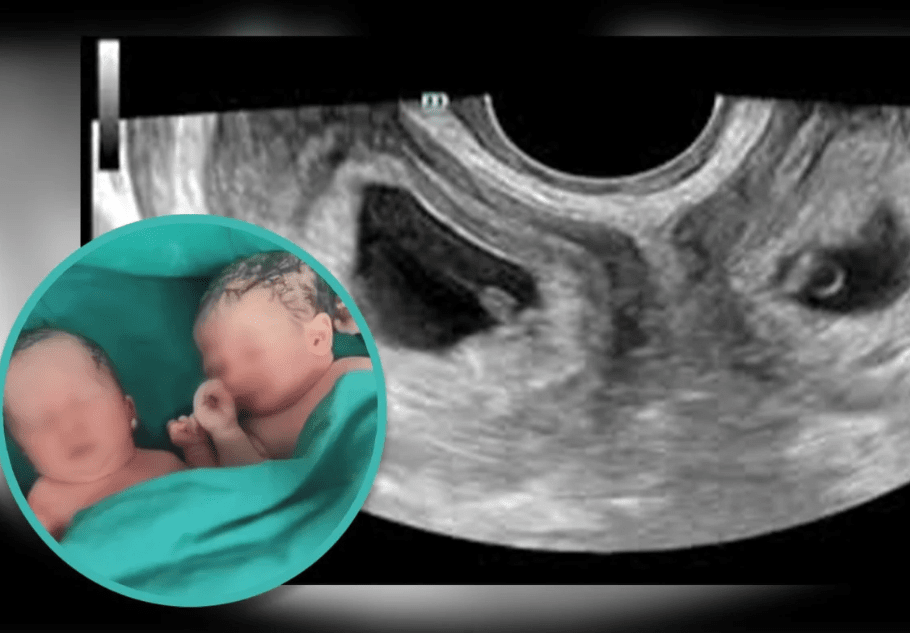

Как пишет South China Morning Post, в сентябре на северо-западе Китая женщина с редким заболеванием — двумя матками — родила близнецов.

Дети женщины, известной только по фамилии Ли, появились на свет с помощью кесарева сечения в Народной больнице Сианя, где назвали это событие "одним на миллион".

По данным больницы, китаянка родилась с двумя шейками матки и двумя матками — это состояние называется удвоением матки и встречается примерно у 1 из 2000 женщин.

"Чрезвычайно редко близнецы зачинаются естественным образом в каждой полости матки, и еще реже их вынашивают", — сообщили в больнице.

Кстати, мальчик родился весом 3 кг 300 г, девочка — 2 кг 500 г..